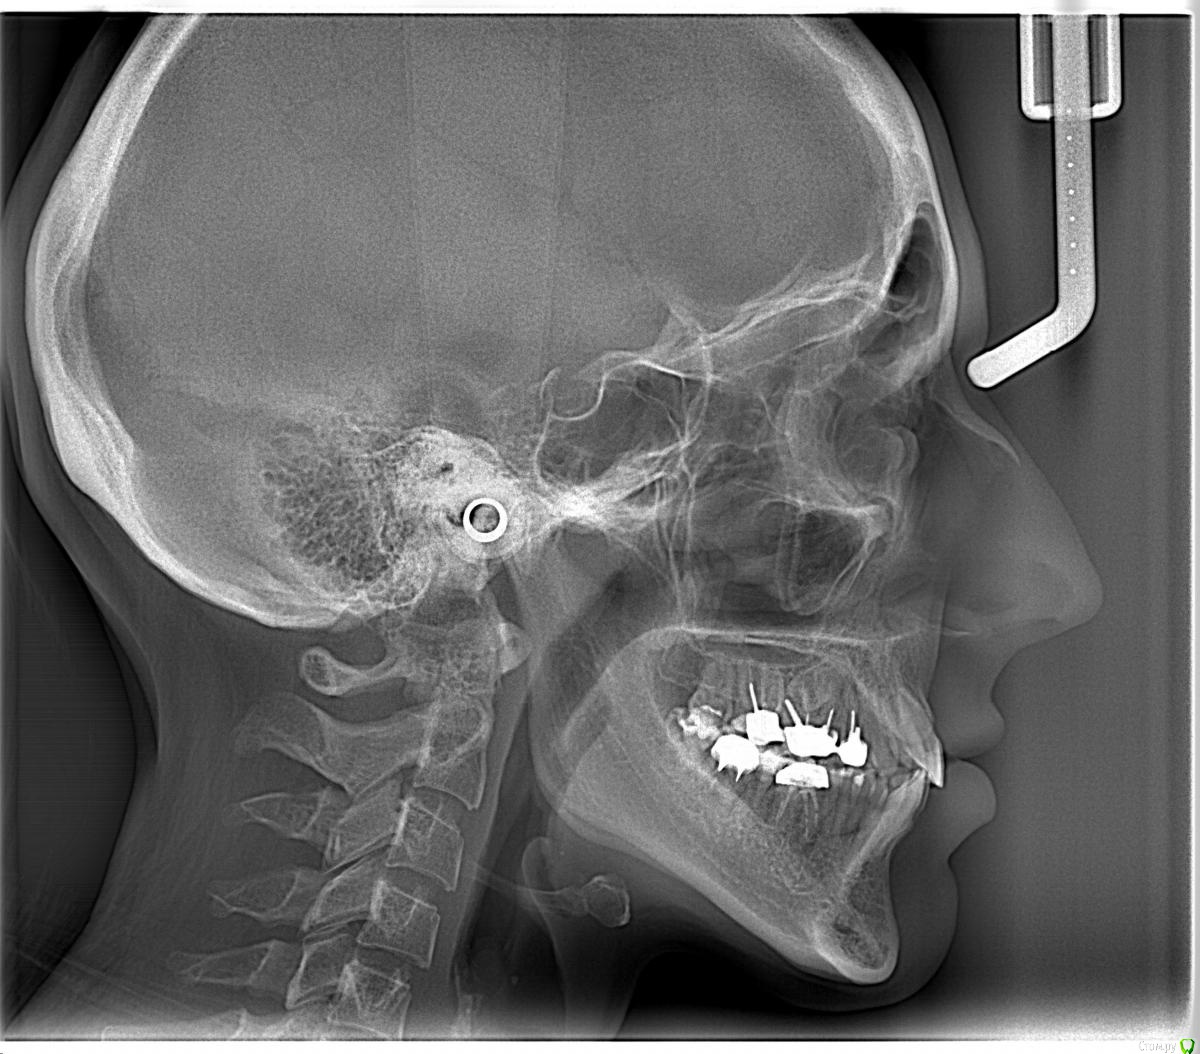

Opdihatop Опубликовано 16 апреля, 2017 Поделиться Опубликовано 16 апреля, 2017 Здравствуйте, коллеги! Что вы думаете по поводу этого случая? Объективно: вертикальный рост, первый костный класс. Незначительная протрузия резцов в/ч, нормальный наклон резцов н/ч. 15 зуб ретенирован. Значительное сужение в/ч, сужение н/ч.Вопросов 2: 1) Тянуть ли 15 зуб? 2) Планирую расширять при помощи SARPE, что делать с образовавшимся местом (которое и так сейчас уже есть)? Мне кажется такие большие реставрации будут некрасивыми. Ссылка на комментарий

Brigita Опубликовано 16 апреля, 2017 Поделиться Опубликовано 16 апреля, 2017 (изменено) Здравствуйте, коллеги! Что вы думаете по поводу этого случая? Объективно: вертикальный рост, первый костный класс. Незначительная протрузия резцов в/ч, нормальный наклон резцов н/ч. 15 зуб ретенирован. Значительное сужение в/ч, сужение н/ч.Вопросов 2: 1) Тянуть ли 15 зуб? 2) Планирую расширять при помощи SARPE, что делать с образовавшимся местом (которое и так сейчас уже есть)? Мне кажется такие большие реставрации будут некрасивыми.1) а куда его?2)Реставрации передних зубов имеется ввиду? Не такой большой промежуток, можно и реставрацию, если виниры не может позволить. расширение на SARPE - в таком возрасте без хирургии маловероятно, Вы же сами знаете, получите зубоальвеолярное небольшое расширение и наклон. Такой тонкий биотип, что там еще с кортикалкой будет. Мосты спаянные, вкладки. Чтобы узнать положение 5го надо КТ сделать, где у него корень - пойдет ли. Он видимо в небной костиА вообще - отдайте ее ортопедам. Она сама то что хочет? Изменено 16 апреля, 2017 пользователем Brigita Ссылка на комментарий